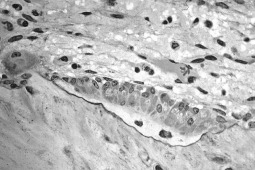

Osteoporoza jest chorobą cywilizacyjną polegającą na postępującym ubytku masy kostnej i zwiększonej łamliwości kości. Choroba ta wbrew obiegowym opiniom dotyczy nie tylko pań po 50. roku życia, ale także mężczyzn, a nawet młodych ludzi – tłumaczy Paweł Pożdał z MZOZ w Słupsku. Początkowo przebiega na ogół bezobjawowo. W późniejszym okresie choroby najbardziej dramatycznymi objawami osteoporozy są złamania kości, w tym niebezpieczne złamania szyjki kości udowej. Złamaniu ulegają często kręgi oraz kości przedramienia w okolicy nadgarstka.